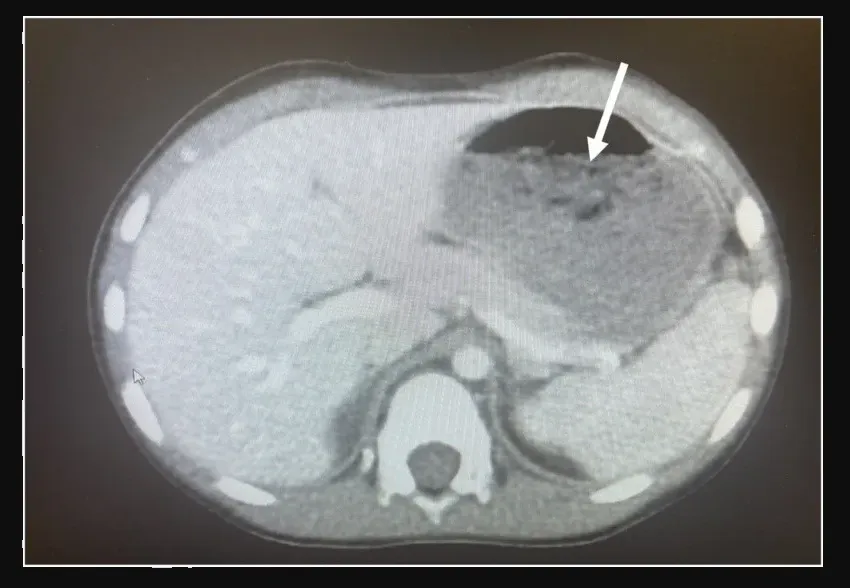

En el hospital, los estudios revelaron que el niño tenía una gran masa, médicamente denominada bezoar, atrapada en el estómago y que ocupaba alrededor del 25% del espacio.

Los doctores decidieron sacar la bola dechicle por la garganta a través de una esofagoscopia mediante múltiples “pasadas”, lo que originó que el niño se quejara de dolor de garganta pero no pasó a mayor problema.